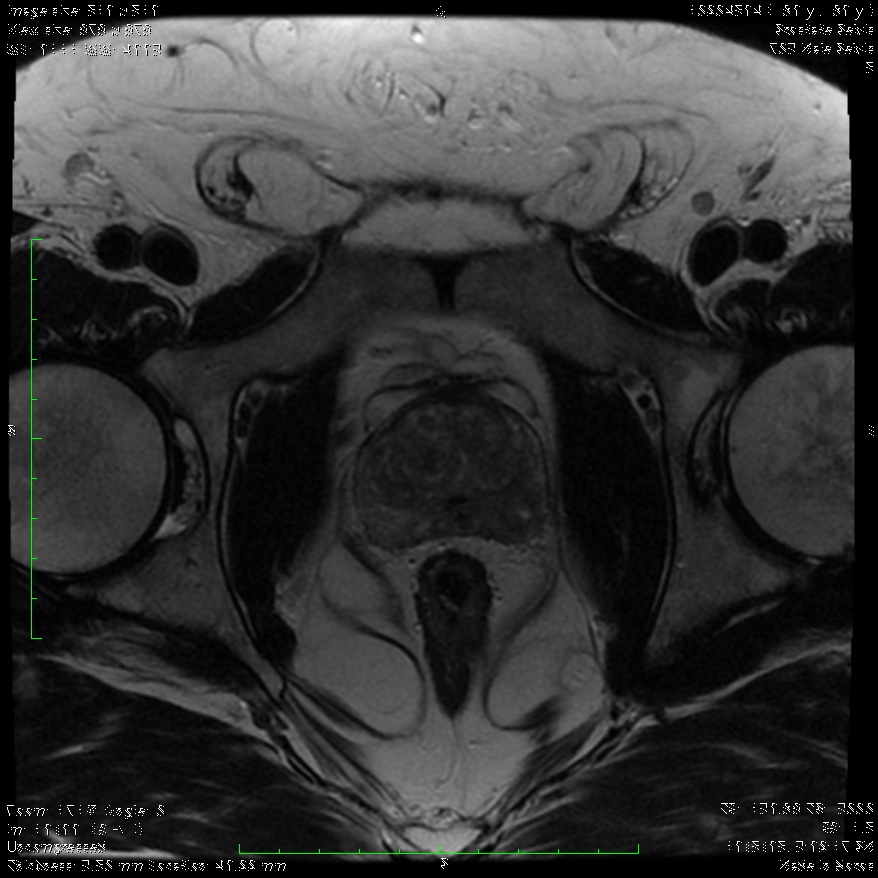

Στη περίπτωση που ο γιατρός εντοπίσει κάποια ένδειξη που θεωρεί ότι χρειάζεται περαιτέρω διερεύνηση, θα καθοδηγήσει τον ασθενή να υποβληθεί σε πολυπαραμετρική μαγνητική τομογραφία (MRI) του προστάτη, προκειμένου να έχει καλύτερη εικόνα της περιοχής.

Χρησιμοποιώντας μια ειδική κλίμακα ταξινόμησης (Prostate Imaging-Reporting and Data System – PI‑RADS) με βάση τα ευρήματα της MRI, ο Ουρολόγος θα αποφασίσει εάν ο ασθενής χρειάζεται να υποβληθεί σε βιοψία.